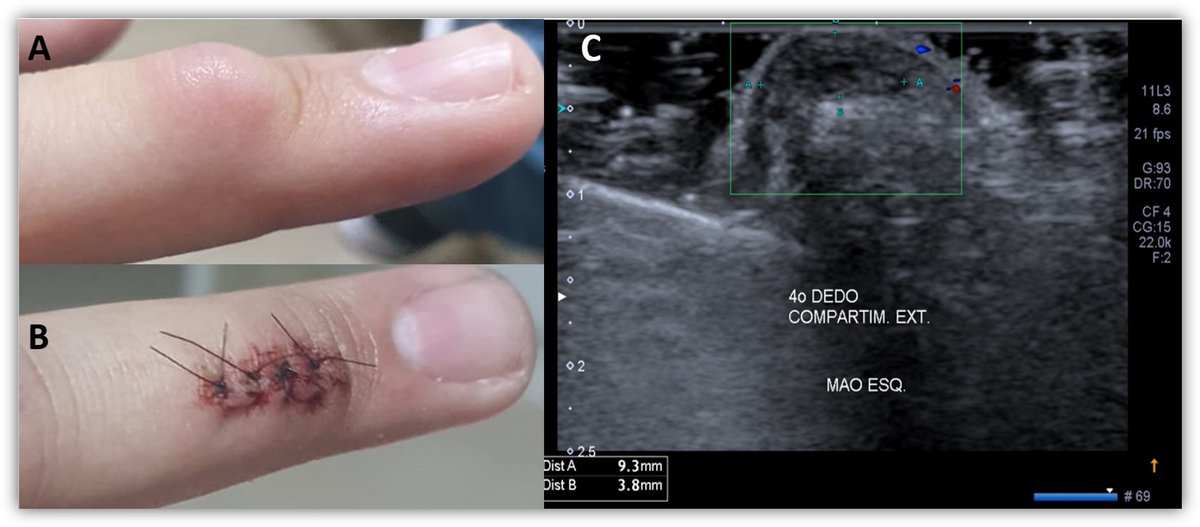

#PathQuiz 🔬

A) Hyperplasia without atypia

B) Hyperplasia with atypia

C) Endometrial polyp

D) Atypical polypoid adenomyoma

#Pathology #GYNPath #Endometrium

Clue in caption 🧐

✅ Endometrial atypical hyperplasia / EIN 🎯

• Defined as a geographical lesion where the glandular volume exceeds the stromal volume.

• Shows significant cytological atypia (loss of polarity, rounded nuclei) distinct from background glands.

• It is a clonal proliferation and a direct precursor to low-grade endometrioid adenocarcinoma.

• Often associated with loss of PTEN or PAX2 expression.